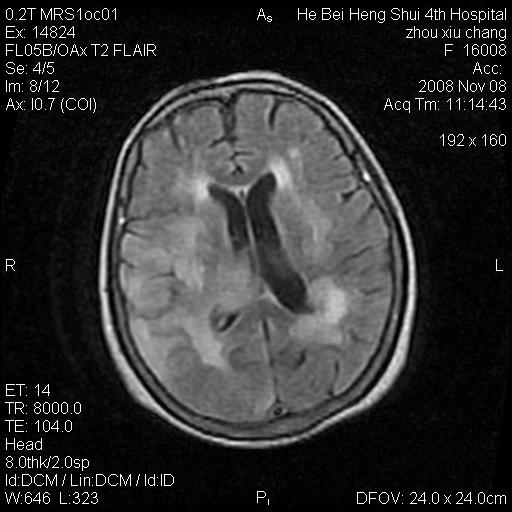

标题: MRI1883:女67岁,半年前曾患脑梗塞,治疗后好转,近3各月精

女67岁,半年前曾患脑梗塞,治疗后好转,近3各月精神恍惚。

形态及整体病灶看起来首先考虑转移瘤或淋巴瘤,但奇怪的是多个病灶周围均未见显著的水肿区,这不符合这两个肿瘤的特点,结合ct表现及患者病史有个人考虑是否有皮层下动脉硬化性脑病伴多发胶质增生可能.

不像占位性病变,考虑脱髓鞘改变

皮层下动脉硬化性脑病伴脱髓鞘改变!